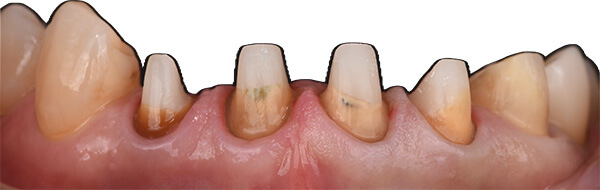

古い被せ物は色や形態が周りと合っておらず、また、被せ物の下には虫歯もありました。